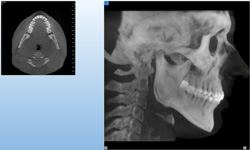

NewTom GiANO

Jedná se o nejnovějším přístroj ze skupiny dentálních hybridních CBCT (3D) + 2D (pan i ceph) systémů. Přístroj umožňuje na základě jediného snímkování vytvořit všechny typy RTG zobrazení, které jsou pro lékaře potřebné.

Používaná technologii tzv. „kuželového paprsku“ a speciální senzory pro minimální zátěž při snímkování pacienta

(o více jak 80% nižší dávka proti klasickému CT).

Pomocí tohoto přístroje je možné zjisti skutečnou situaci v čelistních kostech pacienta tedy množství kosti - můžeme změřit skutečnou šířku i výšku kosti, i kvalitu kosti (hustotu) v místě uvažované implantace. 3D (tříprostorové) zobrazení umožňuje

zvýšit prostorovou představu operatéra ještě před vlastní operací a zároveň pacientovi lépe objasnit a ukázat oblast plánovaného zavedení implantátu.

Pacient „neumí číst“ RTG snímky, ale díky 3D zobrazení vidí „svoji skutečnou čelist“ – např. jak je nízká či úzká, vidí průběh nervu nebo velikost čelistní dutiny, což mu umožní i pochopení nutnosti v některých případech provést pomocné zákroky

ještě před vlastním zavedením implantátu (více - Augmentace - kostní štěp, sinus lift, kostní granulát...).